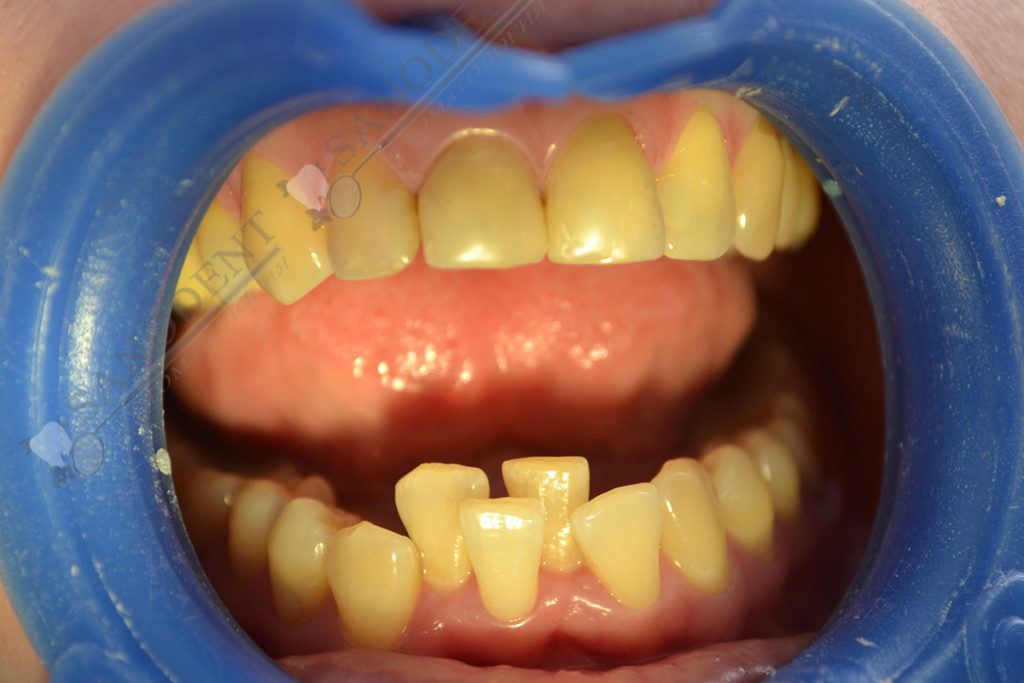

Установка керамических виниров и коронок на зубы с коррекцией положения зубов на нижней челюсти. Фото до и после, (E-max протезирование винирами и коронками)

- вид до протезирования

- нарушение прикуса

- проблемы прикуса на нижней челюсти